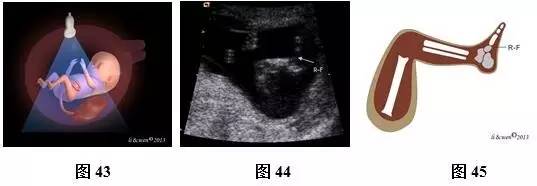

超声扫查方法:声束平面通过一侧上肢作冠状或矢状扫查(图40),即可获得一侧上肢冠状或矢状切面(图41,42);声束平面通过一侧下肢作冠状或矢状扫查(图43),即可获得一侧下肢冠状或矢状切面(图44,45)。对每一肢体按此方法逐一扫查,不漏检任何一条肢体。

标准切面判断标准:上肢冠状或矢状切面:应显示上臂及其内的肱骨,前臂及其内尺、桡骨,手掌及手指。下肢冠状或矢状切面:应显示大腿及其内的股骨,小腿及其内胫、腓骨,足。

主要观察内容:骨的长度、回声强度、数目及形态,肢体是否存在或缺如,手及足形态是否正常。此孕期胎儿呈张手状态,易观察到手指数目。

注:R-H为右手;R-F为右足

图40~45 11~13+6孕周胎儿肢体扫查方法及声像图及模式图。图40上肢扫查方法模式图;图41、42右上肢冠状切面声像图及模式图;图43下肢扫查方法模式图;图44、45下肢矢状切声像图及模式图